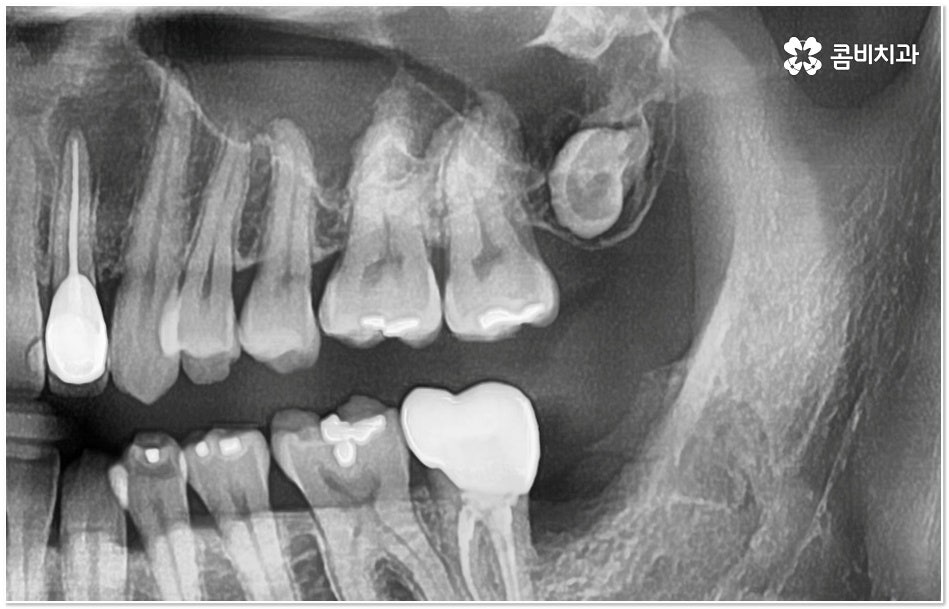

특히 그 중에서도 사랑니와 어금니 사이에 생긴 치아 사이 충치 는 구강 내 가장 안 쪽에 있기 때문에 제 때 발견하기도 어렵고 위치상 치료하기가 쉽지 않아서 병증의 진행 여부 및 상황에 따라 사랑니 뿐만 아니라 어금니까지 발치를 해야 하는 안타까운 상황에 이를 수도 있으니 그 전에 알맞은 대처를 해 주시는 것이 필요할 거예요.

사랑니 같은 경우는 영구치 중에서 가장 마지막에 자라기 때문에 다른 치아와 턱 뼈에 밀려 비좁은 공간에 누운 채 자리를 잡거나 부분적으로만 나오는 등 비정상적으로 맹출될 가능성이 높은 치아인데, 그렇지 않아도 위치상 관리가 잘 되지 않는 곳에서 앞 어금니와의 사이에 작은 틈새가 생기게 되면 음식물이 더욱 잘 끼고 빠지지 않으므로 치아 사이 충치 가 쉽게 발생하게 되는 거예요.

사랑니와 어금니 인접면에 치아 사이 충치 가 발생할 경우 육안으로도 보기 힘들 뿐 아니라 엑스레이를 찍었을 때에도 쉽게 발견하기 힘들 수 있기 때문에 초기에 알아차리지 못하고 치료 시기를 놓치는 경우가 종종 생기며 손상 정도가 많이 심각하거나 위치상 사랑니 발치 후에도 뿌리 끝 염증이 매우 심하거나 치아 사이 충치 로 손상이 심해 치료가 불가능한 케이스의 경우 불가피하게 어금니까지 발치를 해야 할 수 있으므로 이와 같은 상황에 이르지 않도록 평상시에 정기 검진을 꼬박꼬박 받아주는 것이 조기 대처 및 예방 등에 있어 여러 모로 유리하다고 할 수 있습니다.

특히 사랑니가 나오는 시기인 10대 후반부터 20대 초반에 3D CT와 같은 정밀 진단 장비를 통해 사랑니 검진을 한 번 꼼꼼하게 받아보시고 구강 상태를 세세하게 파악한 뒤 비스듬하게 누워있거나 잇몸뼈 속에 매복이 되어 앞 어금니 및 전체 구강 건강에 좋지 않은 영향을 지속적으로 줄 수 있는 상황이라고 판단이 된다면 발치 계획을 세워서 미리 뽑아주는 것도 좋을 거예요.